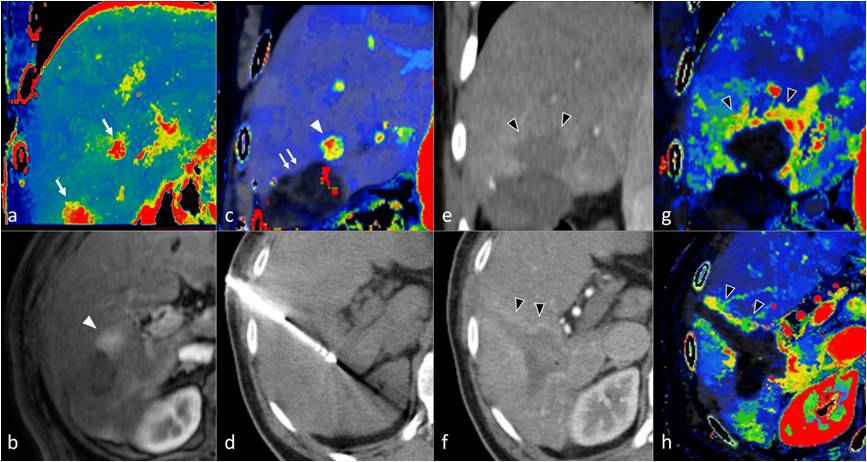

From a technical standpoint, CTLP is based on the analysis of a dynamic CT dataset consisting of sequential images of the liver acquired over time following the injection of IV contrast medium [83,85]. Specialized software is employed to extract functional information from the image dataset by measuring the change of attenuation of liver tissue and reference input vessels over time and generating corresponding attenuation time curves. Perfusion parameters are derived, either by directly fitting the attenuation time curve of each point of liver tissue (model-free approach) or by implementing complex pharmacokinetic models (model-based approach). The results are presented as parametric maps with a color scale (Figures 8 and 9). A variety of pharmacokinetic models have been employed in the past for CTLP analysis, and can differ in the number of inputs, compartments, and fitting method. Nevertheless, most modern commercial applications implement a dual input, dual compartment model using the deconvolution method, which best approximates the perfusion characteristics of the liver. While perfusion parameter names and perfusion analysis models are vendor-specific, most manufacturers provide parameters pertaining to blood flow (BF), blood volume (BV), mean transit time (MTT), and vessel permeability (PS), as well as hepatic arterial blood flow (HaBF), portal liver perfusion (PLP), and their ratio (hepatic arterial fraction—HAF or hepatic perfusion index—HPI). Other perfusion parameters are usually reported in conjunction with MRI perfusion studies (Table 6).

Figure 8. CT perfusion allows the accurate identification and characterization of HCC lesions. In this 69-year-old patient with cirrhosis, a 12-mm nodular lesion in the right liver lobe (arrow) can be easily distinguished from surrounding liver parenchyma on CT perfusion (a–d), with higher values on the Blood Flow (a), Arterial Liver Perfusion (b), and Hepatic Perfusion Index (d) parametric maps and a lower value on the Portal Venous Perfusion (c) map. The lesion is shown on conventional 4-phase CT (e–h), which was performed on the same day as CT perfusion with arterial phase hyperenhancement (f) and wash-out on the portal-venous (g) and delayed phase (h), which corresponds to LI-RADS 5. BF; Blood Flow, ALP; Arterial Liver Perfusion, PLP; Portal Liver Perfusion, HPI; Hepatic Perfusion Index.

Figure 9. CT Liver Perfusion (CTLP) can complement other imaging modalities for establishing the diagnosis of HCC in difficult cases. This 70-year-old cirrhotic patient was previously treated for HCC with transarterial chemoembolization and presented with a 22-mm subdiaphragmatic lesion in liver segment 8 upon follow-up (arrows). The lesion had a high signal on T2 (a) and T1 (b) MRI. Contrast enhancement (c) and wash-out (d) could not be assessed on MRI due to the presence of artifacts. The MSI map of CTLP (e) clearly shows avid contrast enhancement in the HCC lesion, which was later confirmed with selective angiography (h). Although the Hepatic Arterial Blood Flow (f) and Hepatic Arterial Fraction (g) parametric maps show high values in the HCC lesion, it cannot be differentiated from surrounding parenchyma due to cirrhosis and prior chemoembolization, which alter normal liver hemodynamics. MSI; Mean Slope of Increase, HABF; Hepatic Arterial Blood Flow, HAF; Hepatic Arterial Fraction.